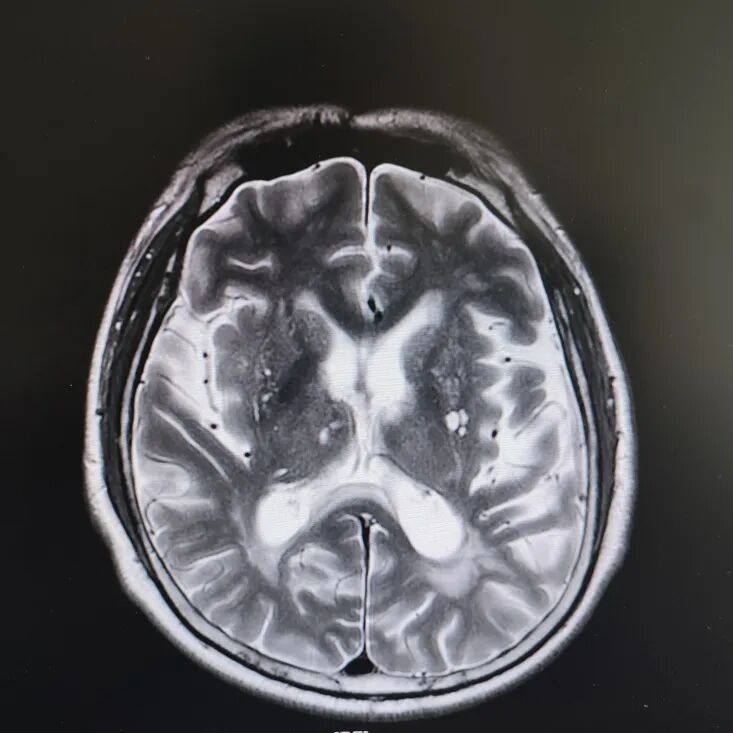

病房里還有另一位患者,來的時候情況更讓人揪心:反應(yīng)遲鈍,表情呆滯,行動緩慢。頭顱核磁顯示腦萎縮明顯,但查體發(fā)現(xiàn)肌張力、計算力、記憶力、定向力均正常,不符合典型血管性癡呆或阿爾茨海默病表現(xiàn)。

患者頭部磁共振影像

憑著多年診治疑難雜癥的豐富經(jīng)驗,趙主任敏銳地意識到這“癡呆”可能是假象,背后另有隱情。他果斷建議進一步做特殊感染篩查。果然,檢查證實這位患者同樣是感染了蒼白密螺旋體!經(jīng)過精準的抗感染治療,奇跡發(fā)生了:患者的反應(yīng)變快了,眼神靈活了,走路也恢復(fù)了正常步態(tài)。最終的診斷是“麻痹性癡呆”——一種由神經(jīng)梅毒引起的、可治療逆轉(zhuǎn)的“癡呆”類型!